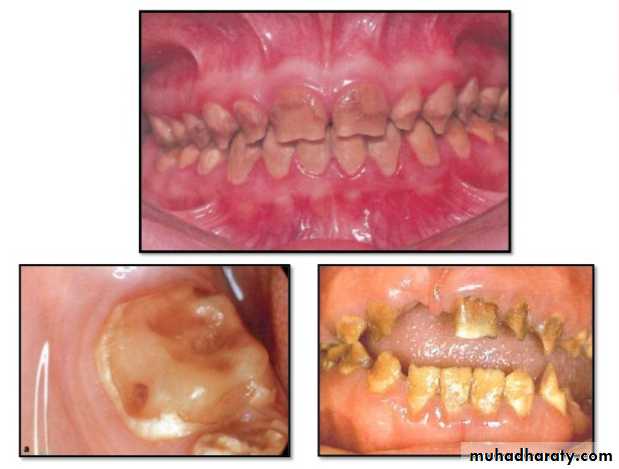

• Dentinogenesis Imperfecta: Is an inherited disorder of dentin formation due to autosomal dominant disturbance.

Affects both primary&permanent dentition.

Blue to brown discoloration with distinctive translucence.

Enamel frequently separates easily from underlying defective dentin.

Dentinogenesis Imperfecta(Hereditary Opalascent Dentin)

Radiographically:

Bulbous crownsCervical constriction

Thin roots

Early obliteration of roots canals & pulp chambers.

Treatment:

Prevent loss of enamel& subsequent loss of dentin

through attrition.

Cast metal crowns for posterior & jacket crowns for anterior teeth

Classification:

Type I:occurs in families with Osteogenesis Imperfecta.* primary teeth are more severely affected than permanent teeth.

Type II: never occurs in association with osteogenesis imperfecta,only have dentin abnormalities without bone disease.

Radiographically (Type I& II ):

partial or total obliteration of pulp chambers & root canals by continued formation of dentin.

roots may be short & blunted.

Normal cementum, periodontal membrane & bone .

Type 2large pulp chambers with thin shell of dentin and enamel “shell teeth”

Type III (Brandywine type ): Rare condition, seen in racial isolate of Maryland.

exhibits multiple pulp exposures and periapical lesions in deciduous dentition.

Also known as “Rootless Teeth”. It is a hereditary disease.